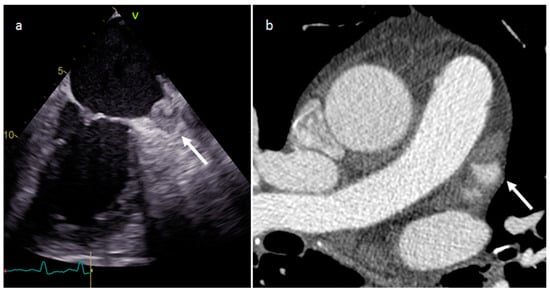

| Coronary artery aneurisms | Adulthood | AV groove | Asymptomatic | Vascular mass | AV groove mass | Dilatation, thrombus, fistula | Vascular enhancement |

| Rhabdomyoma | Fetal life and childhood. Tuberous sclerosis | LV, IVS | Asymptomatic. Rarely flow obstruction, heart failure, arrhythmias | Intramyocardial masses, frequently multiple | Homogenous, slightly echogenic | Attenuation similar to myocardium | Iso T1w, iso-hyper T2w, no or minimal enhancement |